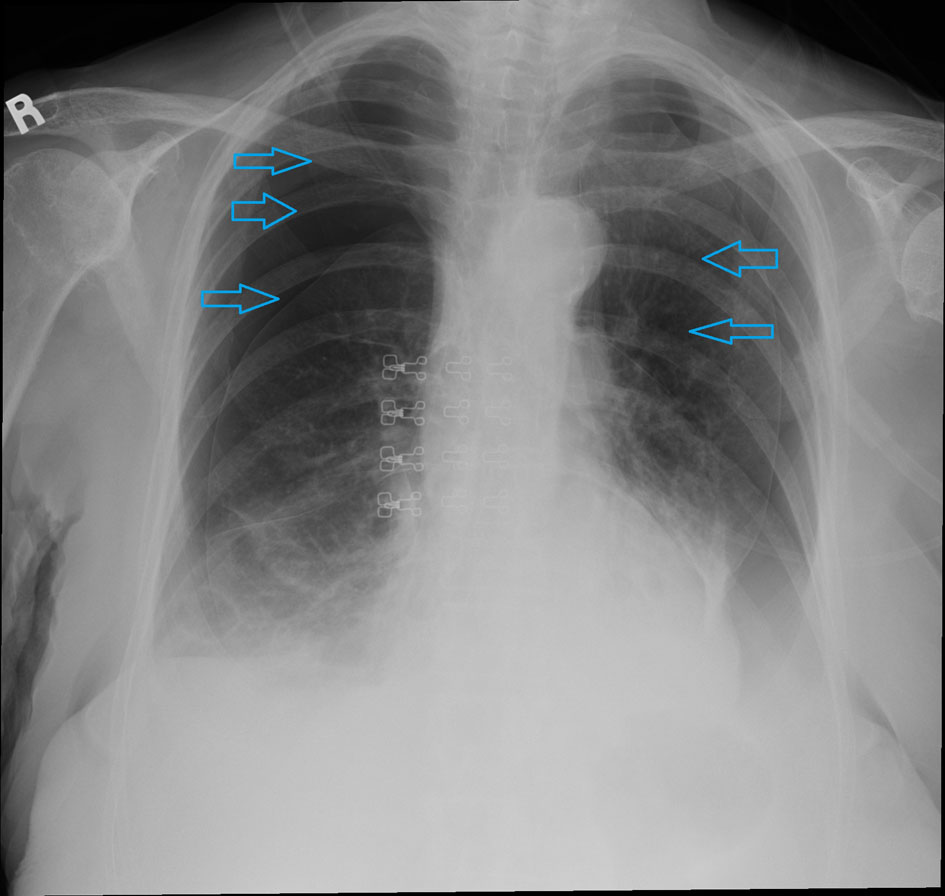

An 85-year-old Caucasian female nonsmoker with a past medical history significant for angiosarcoma presented to emergency department with a 2-week long history of progressively worsening shortness of breath. The patient’s angiosarcoma originated from the scalp and had extension into the face with metastasis to the lung. The patient previously had surgery to remove the angiosarcoma in the scalp and had reconstruction done. The patient was further treated with radiotherapy for the metastasis to the lung, with the latest treatment administered 2 weeks prior to her presenting to the emergency department. She had received a total of 12 MeV electrons delivered to the site with a dose of 57.2 Gy fractions in 20 fractions over a several week interval. She reported that her shortness of breath had been getting progressively worse and was associated with a productive cough. She denied orthopnea, paroxysmal nocturnal dyspnea, chest pain, palpitations, fevers, chills, or changes in weight. On physical exam, blood pressure was 182/89 mm Hg, pulse was 110 bpm, respiratory rate was 22/min, saturation was 88% on room air, and temperature was 98.3 °F. She was in moderate respiratory distress during examination. There was a large mass on the right cheek and a graft with acanthosis partially healing over the scalp. There were areas of erythema with mild bleeding and raw surfaces on the scalp as well. Lungs examination revealed a resonant chest with a tympanic node overlying the anterior apices, diffuse resonance bilaterally, decreased air entry, and severely diminished breath sounds. Laboratory data showed a hemoglobin of 11 g/dL, hematocrit of 34%, white count of 11,000/μL, platelets of 371,000/μL and an INR of 1. Basic metabolic panel was within normal limits. ECG showed sinus tachycardia. Chest X-ray showed bilateral pneumothoraces at least 50% on the left and 70% on the right (Fig. 1). The patient was diagnosed with radiation-induced spontaneous pneumothorax and bilateral chest tubes were placed by the cardiothoracic surgeon. Patient was discharged home after few days and she was doing fine after 6 months of follow-up.

![]() Click for large image | Figure 1. Chest X-ray demonstrating bilateral pneumothoraces. |